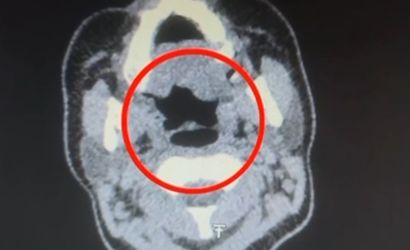

Şüpheli, hastaneye götürülerek iç beden muayenesine tabi tutuldu. Yapılan muayenede, şüphelinin midesinde 50 adet kapsül şeklinde toplamda 500 gram uyuşturucu madde bulunduğu tespit edildi.